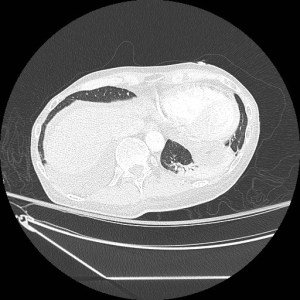

History: 60 year old male with fever, cough, and shortness of breath.

This is complete collapse of the lateral basal segment of the left lower lobe, which can also be describe as partial atelectasis of the left lower lobe. Lobar collapse occurs when an entire lobe of the lung is not aerated. Obscuration of the soft tissue-air interface of the hemidiaphragm with the adjacent lung by the atelectasis is commonly referred to as the Silhouette Sign. Some have argued that this is a misnomer, and that the sign should be called “loss of Silhouette sign,” as the normal “silhouette” can no longer be seen.